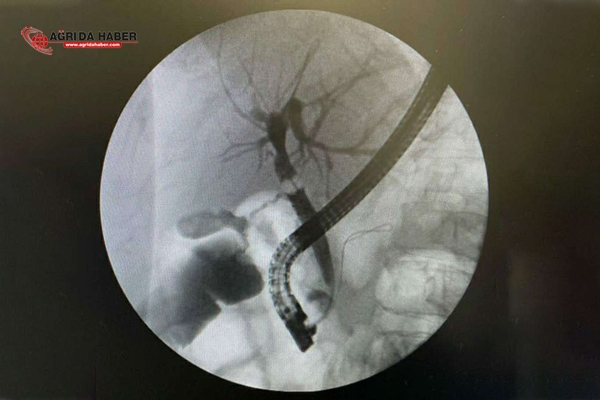

Safra yolları, karaciğer ve pankreas hastalıklarının tanı ve tedavisinde kullanılan ERCP (Endoskopik Retrograd Kolanjio-Pankreatografi) işlemi, Ağrı Eğitim ve Araştırma Hastanesi'nde Gastroenteroloji Uzmanı tarafından ilk defa başarıyla yapıldı.

Hastaneye yatırılarak tedavi altında alınan hastaya ERCP işlemi yapılarak safra yollarındaki taş endoskopik olarak çıkarıldı.

ERCP işlemi Türkiye'de belli merkezlerde yapılmaktadır. ERCP, safra yolları, karaciğer ve pankreas bezinin birtakım hastalıklarında tanı ve tedavisinde kullanılan ileri gastroenterolojik işlemlerden biridir. Endoskopik olarak gerçekleştirilen bu işlemde, ameliyata gerek kalmadan hastanın safra yollarına girilerek işlemler yapılmakta ve safra yollarındaki taşlar temizlenmektedir. Safra yollarında taş bulunan hastamızın safra yollarını temizleyerek başarılı bir işlem gerçekleştirdik. Hastamızın servisteki takibi devam etmektedir.